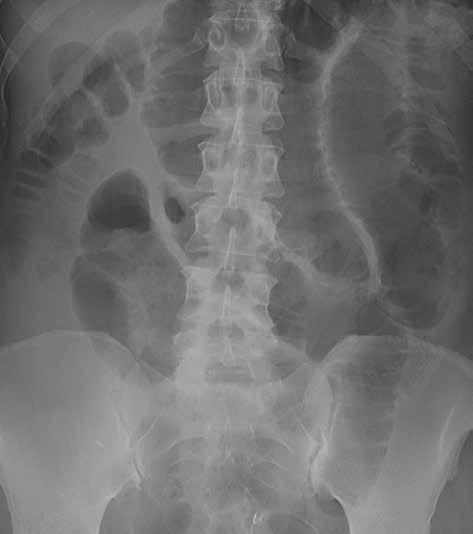

Prostý snímek břicha je stále jednou z nejlevnějších a nejdostupnějších zobrazovacích metod, využívaných při vyšetření nemocných s náhlou příhodou břišní. I když jeho význam klesá a dnes toto vyšetření nelze považovat za „metodu první volby“, má přesto i v době výpočetní tomografie (CT), ultrazvuku (UZ) a MR (magnetické rezonance) využití při podezření na střevní obstrukci či perforaci trávicí trubice, při hodnocení polohy drénů nebo detekci rentgenkontrastního tělesa (obr. 1).

Můžeme provést předozadní snímek vleže na zádech a/nebo zadopřední snímek vestoje v závislosti na indikaci vyšetření. U nemocných ve vážném stavu lze snímkování provádět přímo na lůžku, ovšem za cenu jeho nižší kvality. Prostý snímek břicha vleže na zádech má větší výpovědní hodnotu a standardně i vyšší kvalitu. Přesněji na něm můžeme posoudit šířku lumen tenkého i tlustého střeva. Vzduch tvoří negativní kontrast, který umožní částečně hodnotit šíři střevní stěny i řas. Lépe než u snímku vestoje lze také zhodnotit rozložení plynné náplně střev, a tím i snáze lokalizovat přechodové zóny (obr. 2).

Obr. 2, 3: RTG snímek břicha vleže a vestoje. Ileus tenkého střeva. Vleže je dobře patrná dilatace kliček tenkého střeva nad 3 cm (2). Tenké střevo odlišíme od tlustého přítomností plicae circulares, které obkružují celý obvod lumen střeva. Vstoje vidíme v tenkém střevě hladinky (3).